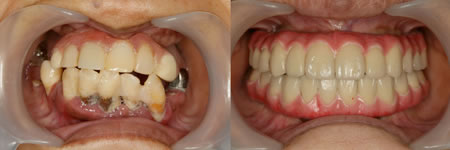

症例21 ALL-ON-4(オールオン4)の症例

主訴:下顎歯周病、上顎無歯顎(40代/女性)

完成図